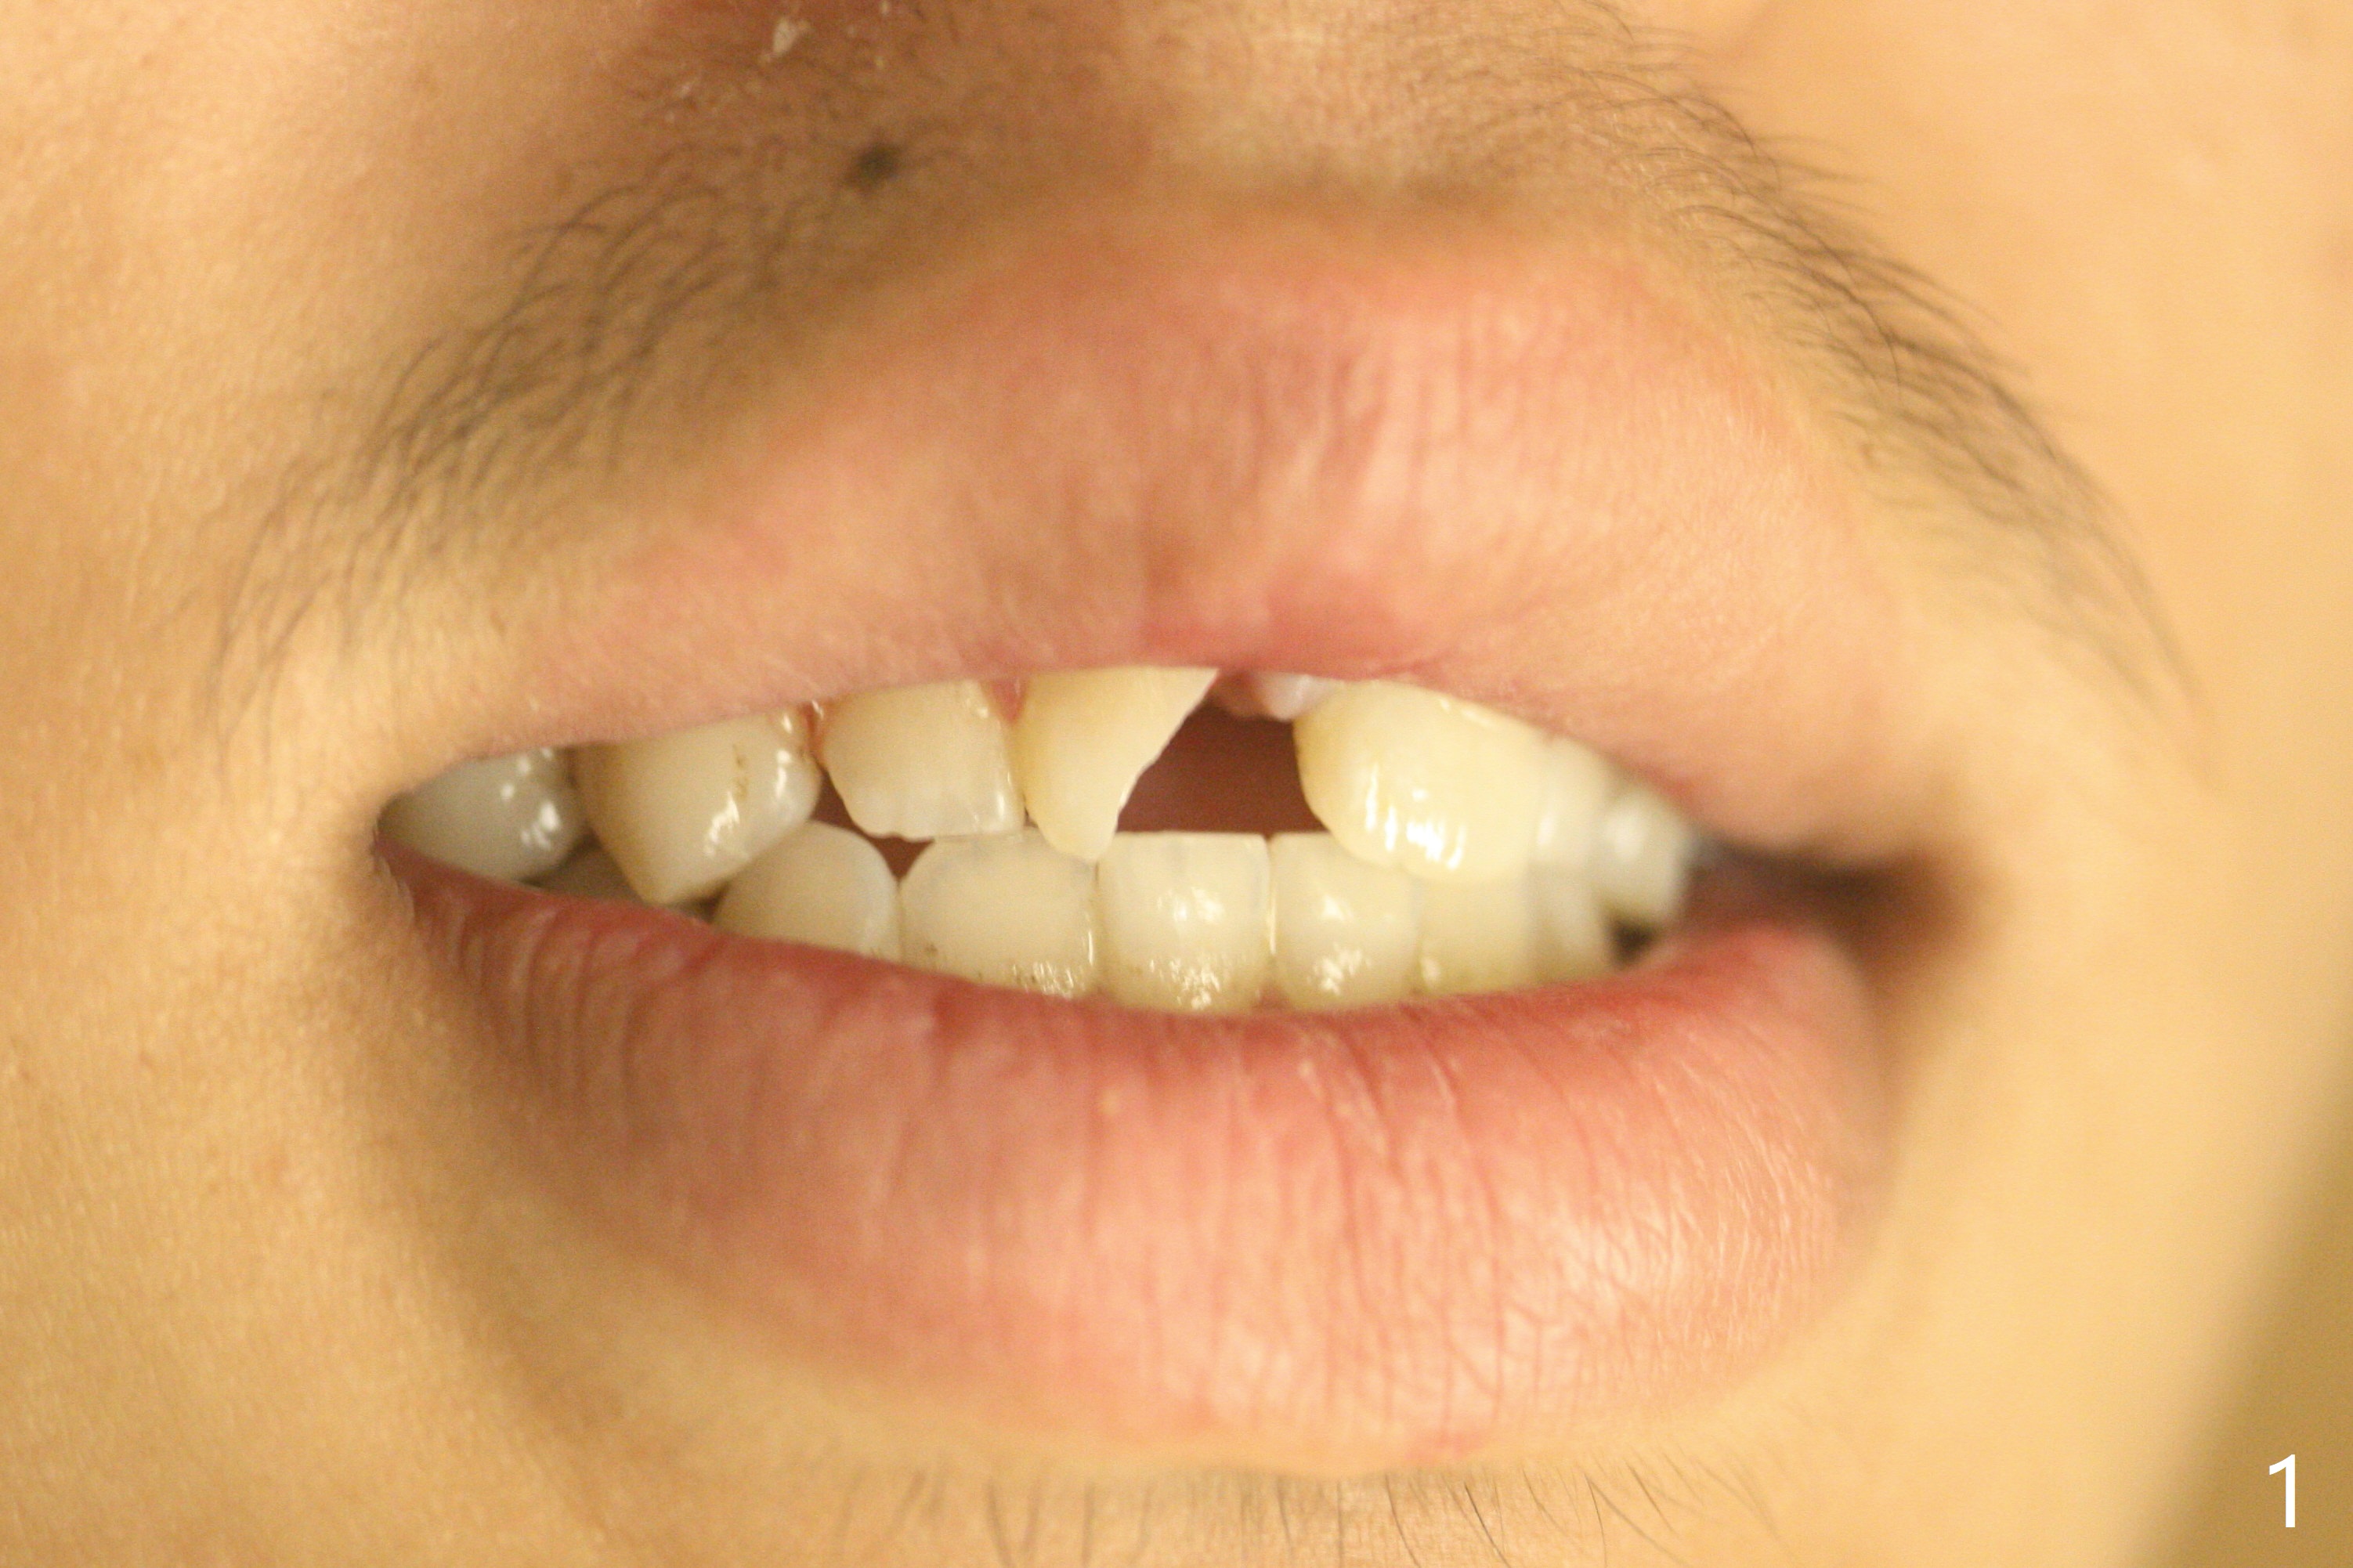

A 16-year-old man fractured the tooth #8 yesterday (Fig.1) with pulpal exposure (Fig.2) and slightly subgingival (Fig.3 <). With 2 gingival retraction cords, rubber dam and floss, the mesial margin is exposed (Fig.4). The mesial pulpal horn is increased slightly with a 330 bur with minimal pulpotomy. MTA is applied (Fig.5 <). A curette is placed over the MTA for hemostasis while it is setting. RelyX Ultimate Adhesive Resin Cement bonding is used to reattach the fracture fragment in place (Fig.6,7). Pulpal vitality will be monitored. A crown will be placed if the tooth discolors due to MTA and the pulp remains vital. Mineral trioxide aggregate (MTA), composed mainly of tricalcic silicate, tricalcic alluminate, bismuth oxide, is a particular endodontic cement. It is made of hydrophilic fine particles that harden in the presence of dampness or blood. The re-attached tooth remains asymptomatic 9 days postop (Fig.8) when he returns for prophy.

16岁男孩,昨天右上中切牙撞击电脑发生折裂(图一),近中牙髓角暴露(图二),裂缘稍微龈下(图三 <),使用两个牙龈牵拉线,橡皮障和牙线,近中折裂边缘暴露(图四)。你会如何处理?使用330钻头稍微扩大髓角开口,去除少量牙髓,填入微量MTA (图五<),希望形成新的牙本质,关闭开口,维持牙髓活性。出血控制后,应用树脂粘合剂将断片固定于原位(图五,六,七)。术后9天牙齿无症状(图八),病人回来洗牙。